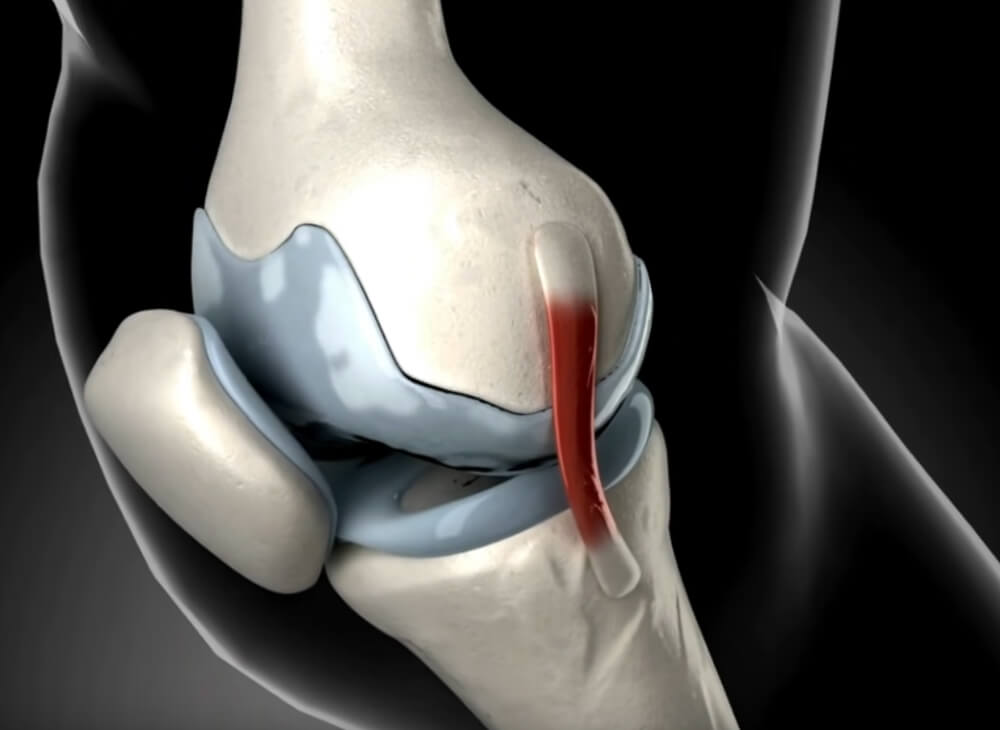

Tussen de gewrichten zit hetkraakbeen.

Dit kraakbeen is een soort beschermlaag voor de gewrichten.

Dit kraakbeen wordt van voedingsstoffen voorzien door gewrichtsvloeistof.

Als je het gewricht beweegt, wordt er meer gewrichtsvloeistof geproduceerd, en wordt het kraakbeen beschermd tegen uitdroging.

Te weinig of verkeerde beweging zorgt er echter voor dat het kraakbeen uitdroogt en broos wordt.

Deze uitdroging zorgt ervoor dat het kraakbeenweefsel geleidelijk afbreekt.

Als gevolg hiervan kan het kraakbeen de gewrichten niet meer voldoende beschermen.

Dit komt doordat de "kraakbeenbuffers" tussen de gewrichten verdwijnen.

Zonder deze buffers schuren de gewrichten "bot tegen bot" bij elke beweging.

Dit leidt tot ernstige gewrichtspijn en staat bekend als artritis.